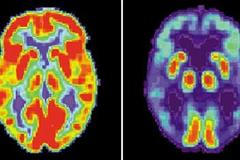

Alzheimer ja tak složitá a komplexní nemoc, že jeden lék, který by ji vyléčil, nebude existovat nikdy. Spíš to bude kombinace léků, které budou zasahovat na několika úrovních, říká lékař Aleš Bartoš.